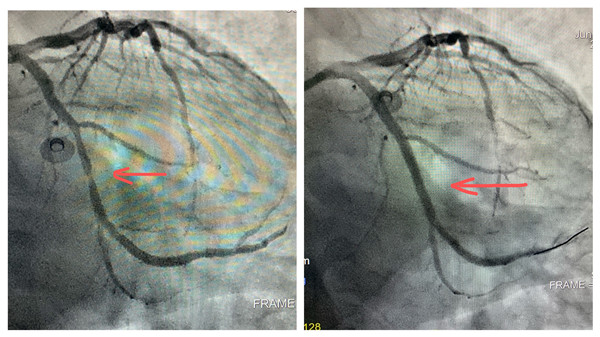

心血管内科邓捷主任医师提前查阅患者资料,积极组织导管手术室、心内科重症监护室,做好接收危重患者的准备。于2021年6月3日,患者辗转数小时航班抵达西安咸阳国际机场,由机场直接到西安交通大学第二附属医院大明宫院区心血管病院导管手术室。此时,已接近凌晨,心血管内科导管手术室还是一片繁忙,邓捷主任医师、倪雅娟主治医师,张明医师早已做好充足的手术准备,护师周媛,护士辛立伟、徐一涛提前备齐手术抢救仪器耗材。接入患者后,冠脉造影结果显示:冠脉三支血管均存在病变,回旋支最严重处堵塞90%,可见当时引起患者心梗的“元凶”就在于此,此时进行血运重建,患者极有可能引起心律失常等一列问题,有预见性的快速精准治疗和术中观察显得极为重要,简单商讨后在医护默契配合下,为患者回旋支植入支架1枚,术中患者生命体征平稳,术后自述胸痛症状减轻。转入心内重症监护室(CCU),CCU主管护师祁雪丽,护师王芳、关晨维,住院总医师马维东,接入患者后,严密观察患者术后各项指标,积极完善患者术后相关后续治疗及护理。此时,已是6月4日凌晨,远在西藏阿里的朱参战主任医师还牵挂着这位年轻患者的安危,经过全科配合,患者入院到罪犯血管开通,仅用时25分钟。